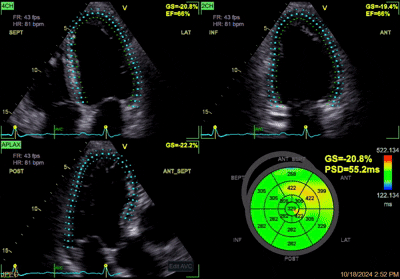

Analiza longitudinalne deformacija miokarda (strain i strain rate)

Napredna ultrazvučna procjena funkcije srčanog mišića.

Evaluacija ishemijske bolesti srca

Procjena i anatomije i funkcije srčanih kaviteta

Procjena dijastolne funkcije i detekcije subkliničke dijastolne disfunkcije